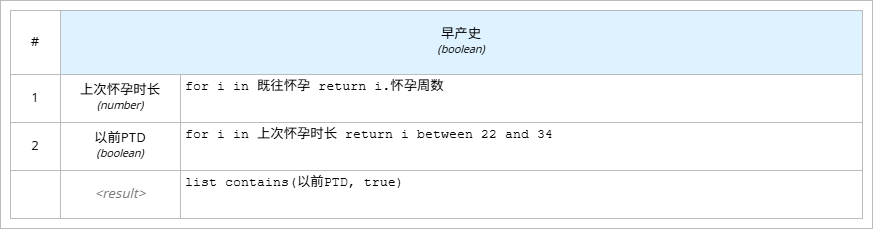

l “早产史”即通过2次循环“既往怀孕”中的怀孕周数、怀孕时长判断孕妇是否会早产。使用上下文的盒装结构,使用2个键值依次对数据进行筛选,最终判断。